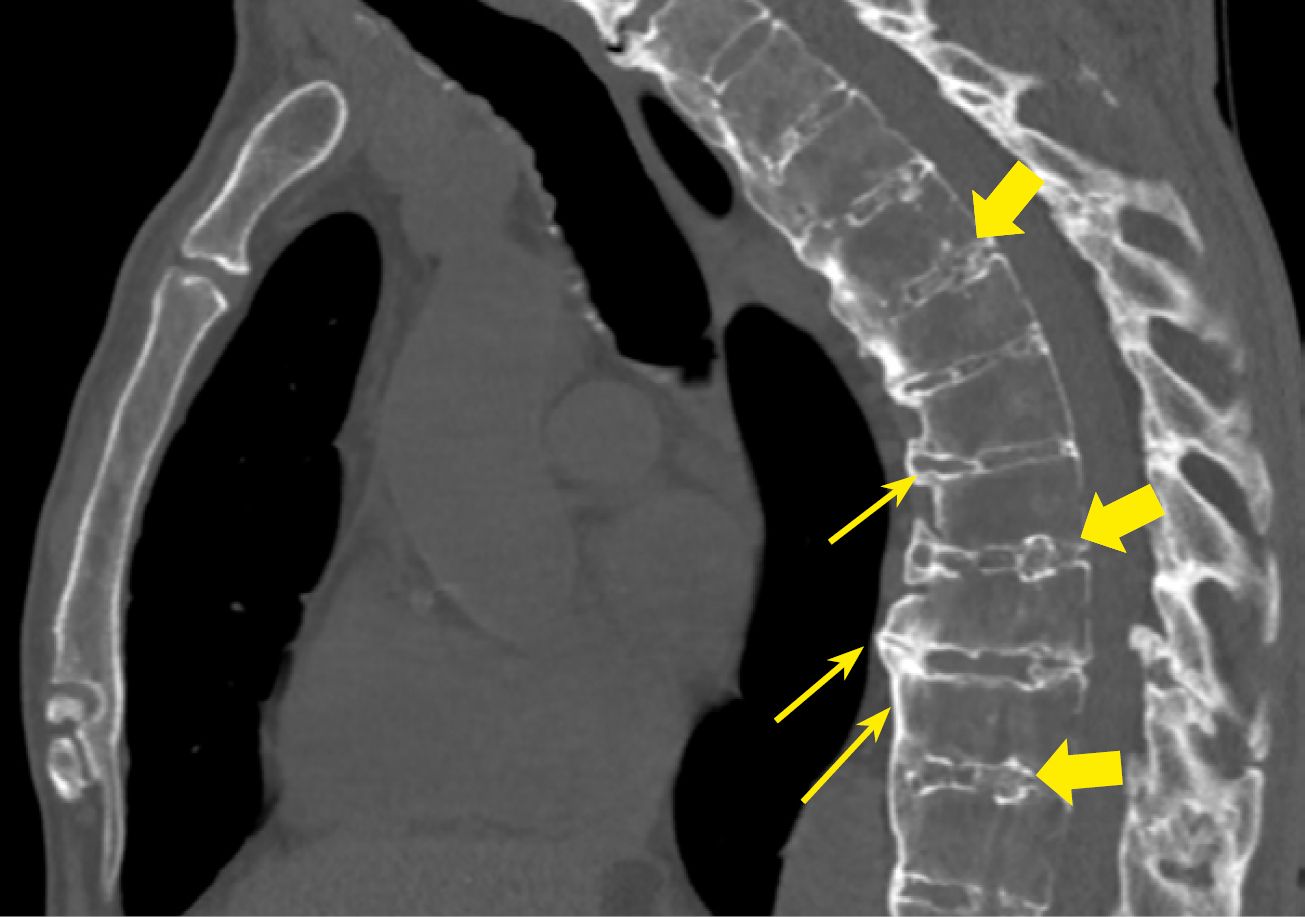

Рисунок 5. МСКТ пациента А. с акромегалией 37 лет, сагиттальная проекция. Остеохондроз грудного отдела позвоночника. Остеофиты по контурам тел позвонков, формирующие «костные мостики» (стрелки), клиновидная деформация тел позвонков, снижение высоты межпозвонковых дисков, участки обызвествления в межпозвонковых дисках (толстые стрелки).

Figure 5. MSCT of patient A. with acromegaly, 37 years old, sagittal view. Osteochondrosis of the thoracic spine. Osteophytes along the contours of the vertebral bodies, forming "bony bridges" (arrows), wedge-shaped deformity of vertebral bodies, decreased height of intervertebral discs, areas of calcification in intervertebral discs (thick arrows).

В нашем исследовании проведен анализ патологии позвоночника и суставов у пациентов с акромегалией. Спондилоартроз выявлен почти у всех пациентов — 95,9%, чуть реже визуализирован ОА реберно-позвоночных суставов 89,8% и ОА грудино-реберных суставов в 75,9% случаев (табл. 3, рис. 2–5).